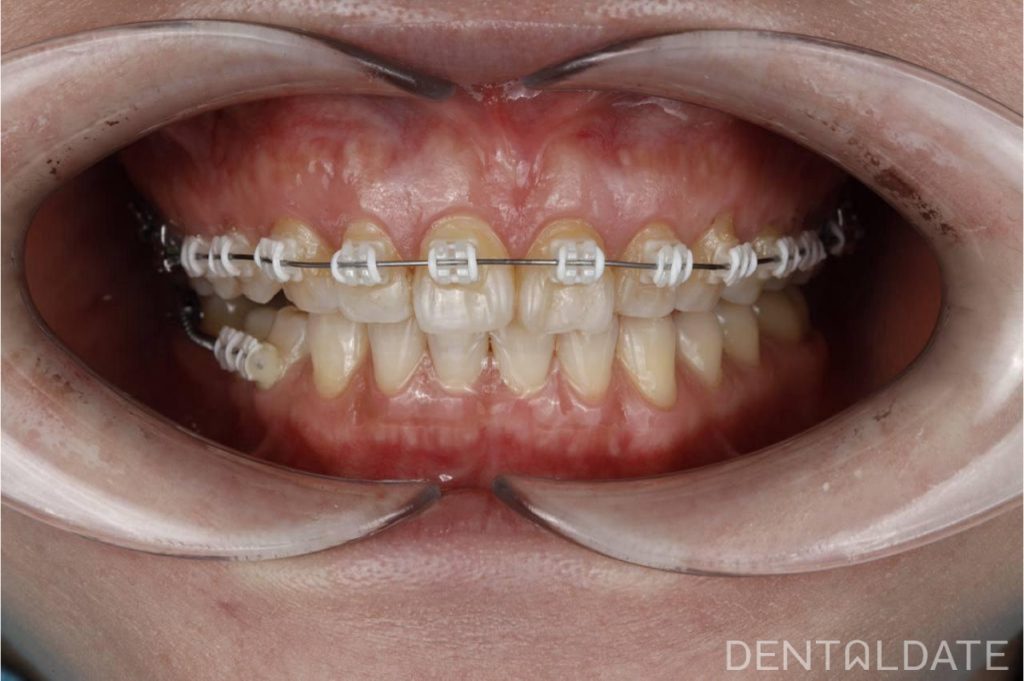

Complex treatment of TMJ arthrosis with orthodontic correction

In this clinical case, we want to demonstrate an approach focused on optimizing treatment timelines for temporomandibular joint (TMJ) osteoarthritis. The patient was diagnosed with TMJ osteoarthritis, confirmed by condylography and CT imaging.

During the splint therapy phase, we observed significant positive changes within just three weeks, including a reduction in symptoms and improved joint function. However, full treatment and joint stabilization require a much longer period.

To make the most of the adaptation phase, we simultaneously initiated orthodontic correction of the upper jaw. This approach allows us to significantly shorten the overall treatment time and achieve faster, more effective results.